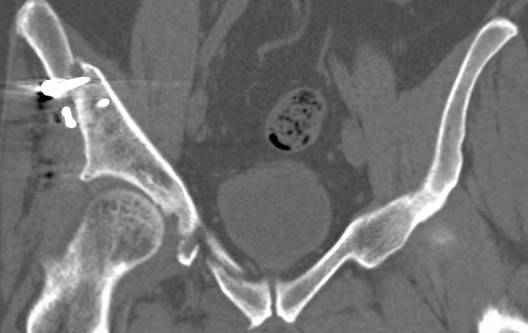

Интересно было бы посмотреть рентгенограммы до операции. У меня впечатление, что я не все вижу, что тут есть... Уважаемые Господа "тазисты" и "тазологи", к какому типу переломов вертлужной впадины по Летурнелю вы бы отнесли это случай?

Из переломов проходящих через крыло и/или заднюю стенку ни простой перелом "передней колонны" (явно имеется пером задней стенки, и не видно перелома седалищной или лонной), ни простой "поперечный", ни ассоциированный "Т-образный" (т.к есть перелом крыла и не видно перелома седалишной), ни ассоциированный "задняя колонна+задняя стенка", на ассоциированный "поперечный+задняя стенка", ни ассоциированный "передняя колонна+задняя гемисфера" (не видно перелома седалищной), ни ассоциированный "обе колонны" (не видно перелома лонной седалищной) не подходят под эту классификацию....

к таковым себя не причисляю, но...обычное дело для нашей страны - выкладывать 3D и не показывать стандартные проекции Judet. Дигност представляет те ракурсы, которые по-его мнению наиболее информативны, более того комп сам достраивает какие-то мелкие повреждения по 3D по своему усмотрению. По данной реконструкции можно предполагать высокий двухколонный перелом с оскольчатыми передней и задней колоннами, оскольчатую высокую переднюю колонну с задним полупоперечником или одно из перечисленных с вовлечение КПС. У меня впечатление за второй вариант, но нужно обследовать нормально - проекции, сканы.

высылаю дополнительно сканы.